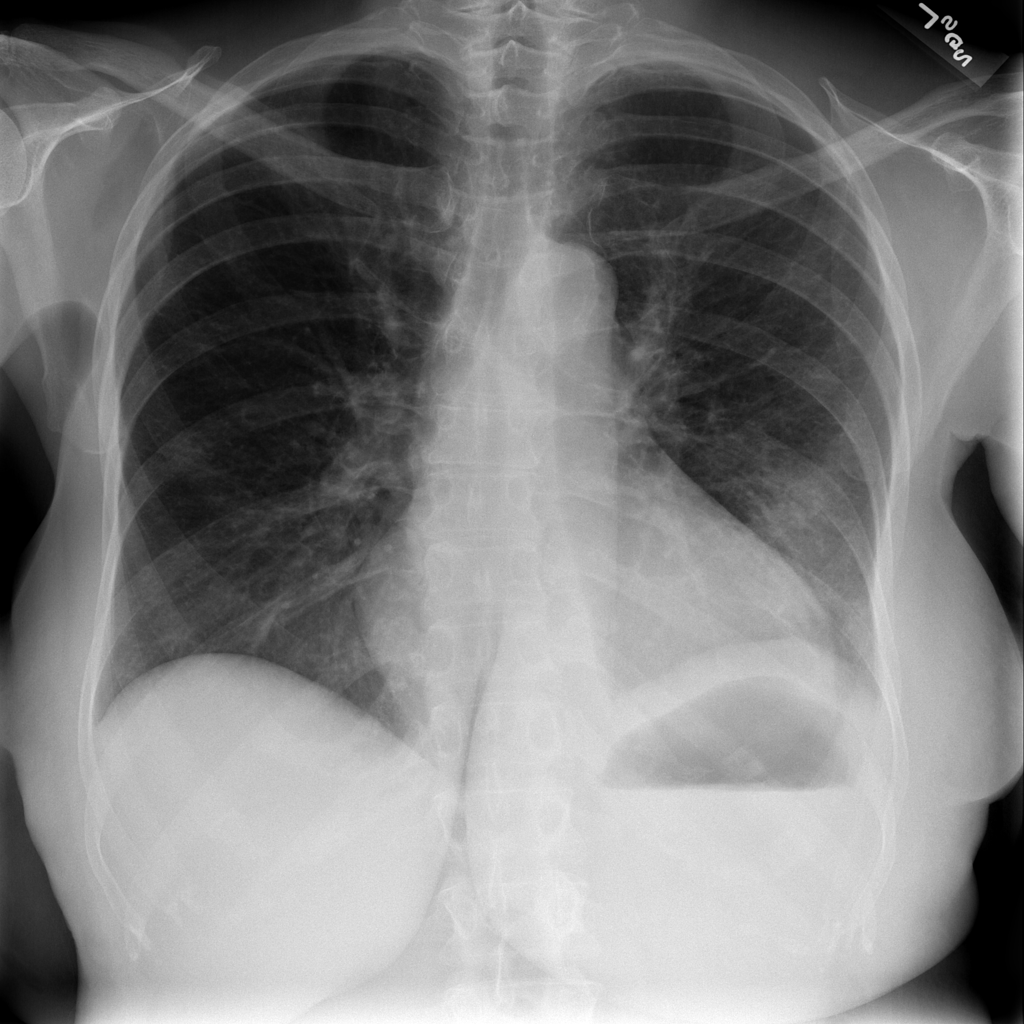

Showing up to 90 reference images for Cardiomegaly.

PAT-F3E7 · IMG-000Cardiomegaly

PAT-F3E7 · IMG-000

PA